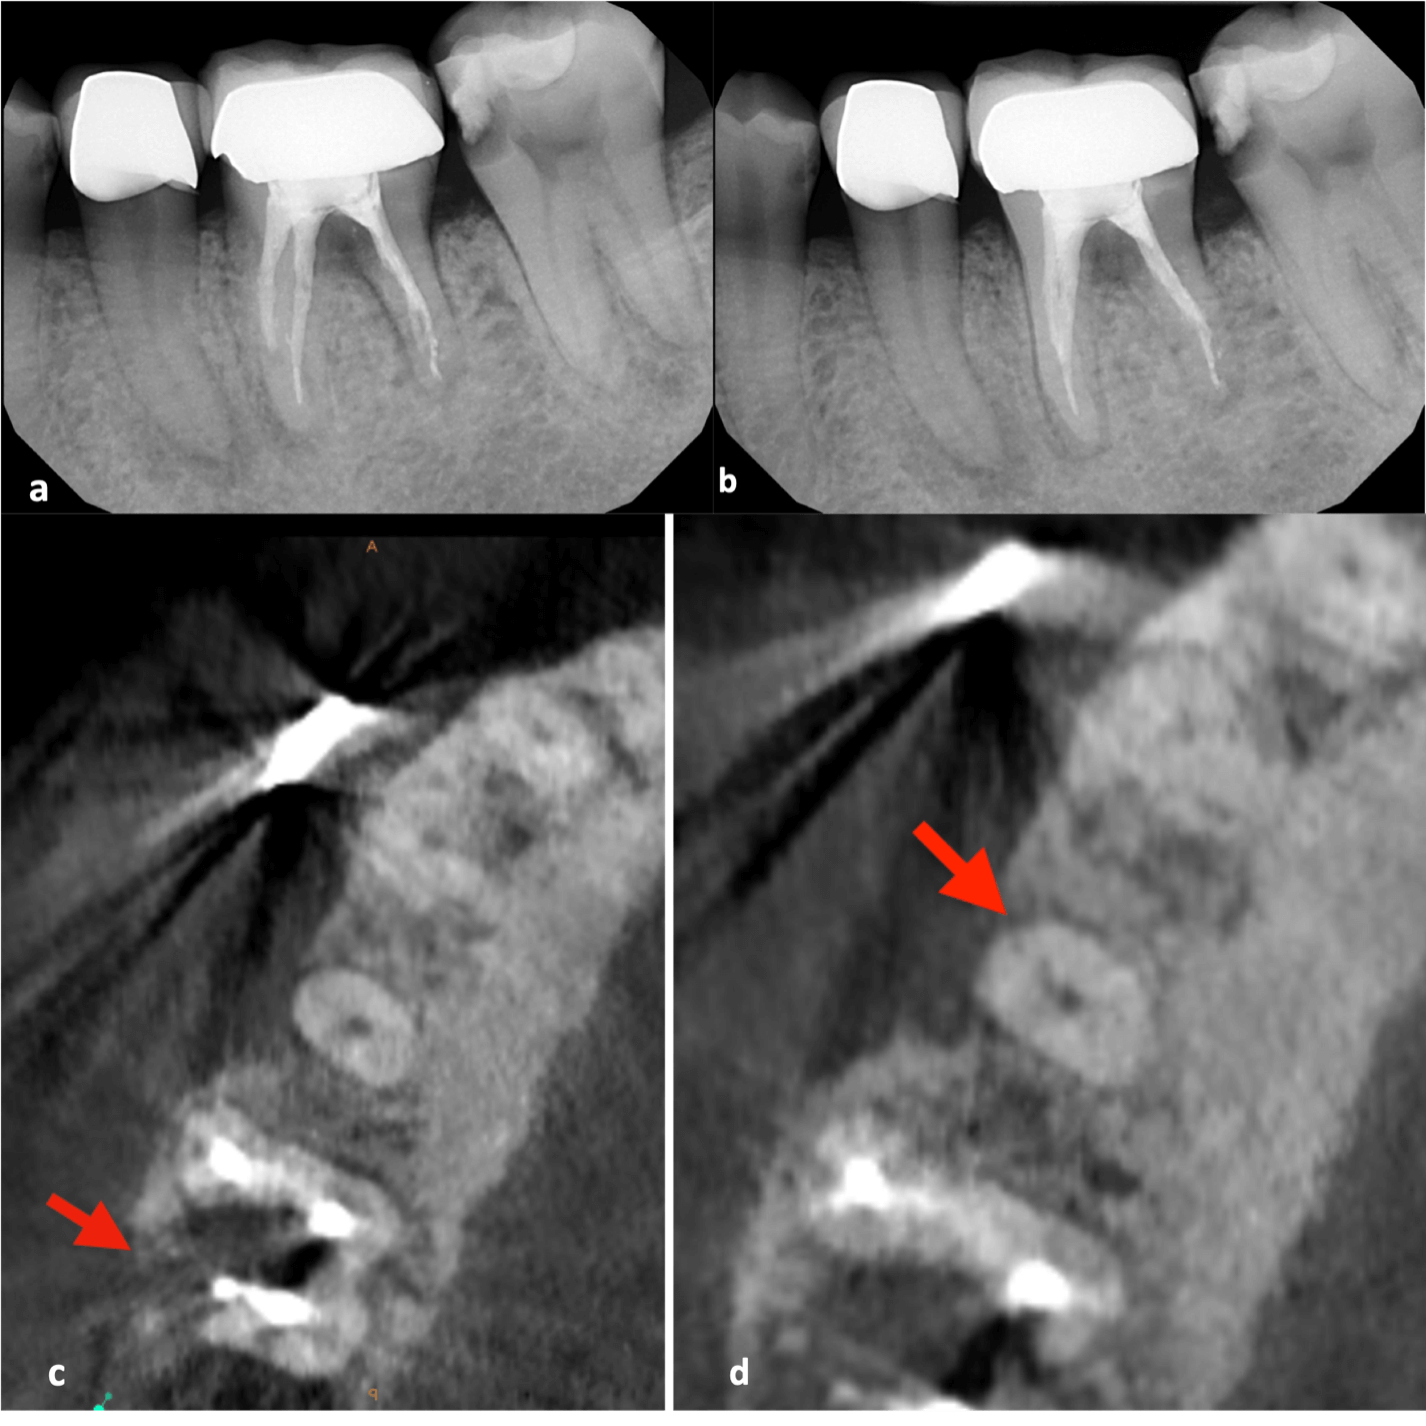

My first “wow” moment with CBCT was during the early years of the technology when scanning a patient after a traumatic dental injury that lead to lateral luxation of the maxillary left central incisor. The CBCT scan was able to produce images that previously had only ever been drawn or imagined. Those stunning 3D images have only gotten better over time. When indicated, 3D imaging provides critical information toward development of the best treatment plan. High-resolution images give endodontists the ability to change course and adapt quickly if needed to achieve better outcomes. Being able to diagnose a predictable failure also avoids unnecessary invasive procedures. For example, cases of root fractures or deep cracks (figure 1). For root canal retreatments understanding the etiology of the disease or failure is critical to obtain a positive outcome. CBCT also aids with enhanced visualization of traumatic injuries, particularly for crown, root fractures and luxation injuries (figure 2). Ultimately, the more accurate and realistic assessments of prognoses, the more predictable and positive outcome for my patients.

a-b. Periapical radiographs from different angles. Patient presented immediate after a traumatic injury to maxillary anterior teeth. Clinical and radi